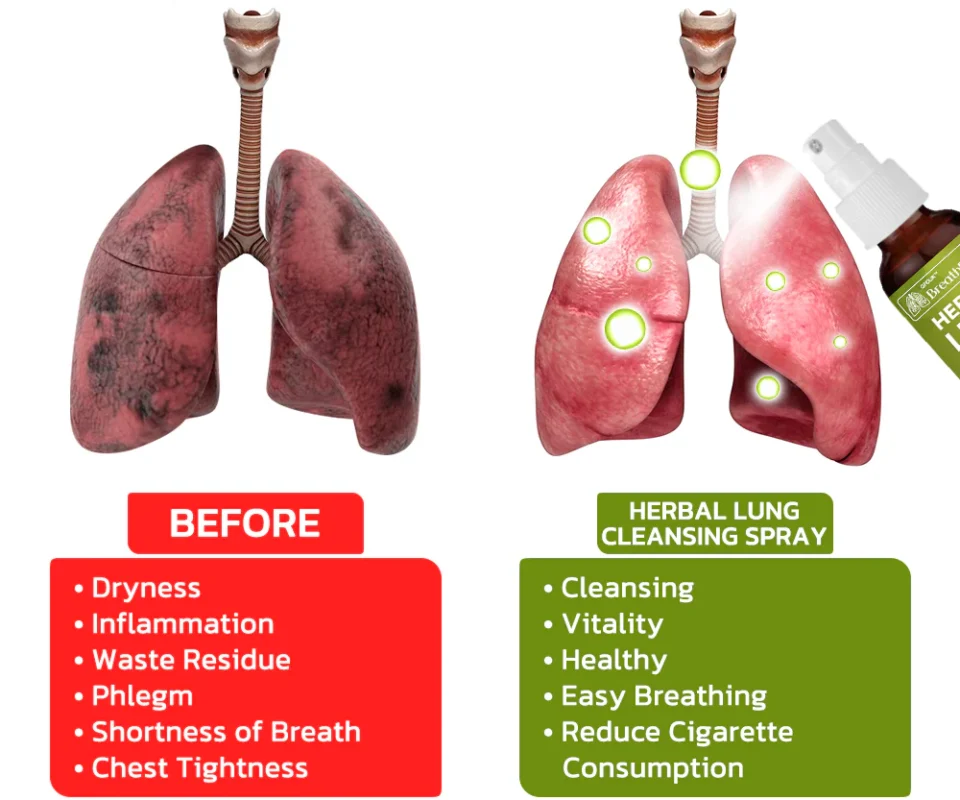

The HZA™️ BreathDetox Herbal Lung Cleansing Spray offers a convenient and effective solution for clearing mucus and waste from the lungs, as well as purifying and cleansing the upper respiratory passages. It is specifically designed to repair damage caused by allergies, asthma, dust, and smoking within a span of 8 weeks. This innovative product provides individuals with weakened respiratory systems an effortless opportunity to restore their breathing capacity.

【Expert】Organic Herbal Fusion – Purify trachea and lungs by eliminating lingering buildup – Restore optimal functionality of alveoli – Regenerate tracheal tissue – Alleviate allergies and asthma symptoms – Enhance the sensation of unobstructed breathing – Provide support for individuals with COPD

Clinical trials and surveys have yielded compelling evidence supporting the effectiveness of this medication in the treatment of chronic pharyngitis, pulmonary nodules, and pulmonary dysfunction. Furthermore, it has demonstrated notable efficacy in managing environmental allergies and asthma. Additionally, thorough verification has established the significant role of the spray in both treating and preventing the consequences of pulmonary inflammation. These findings contribute to the growing body of evidence highlighting the medication’s effectiveness across a range of respiratory conditions.